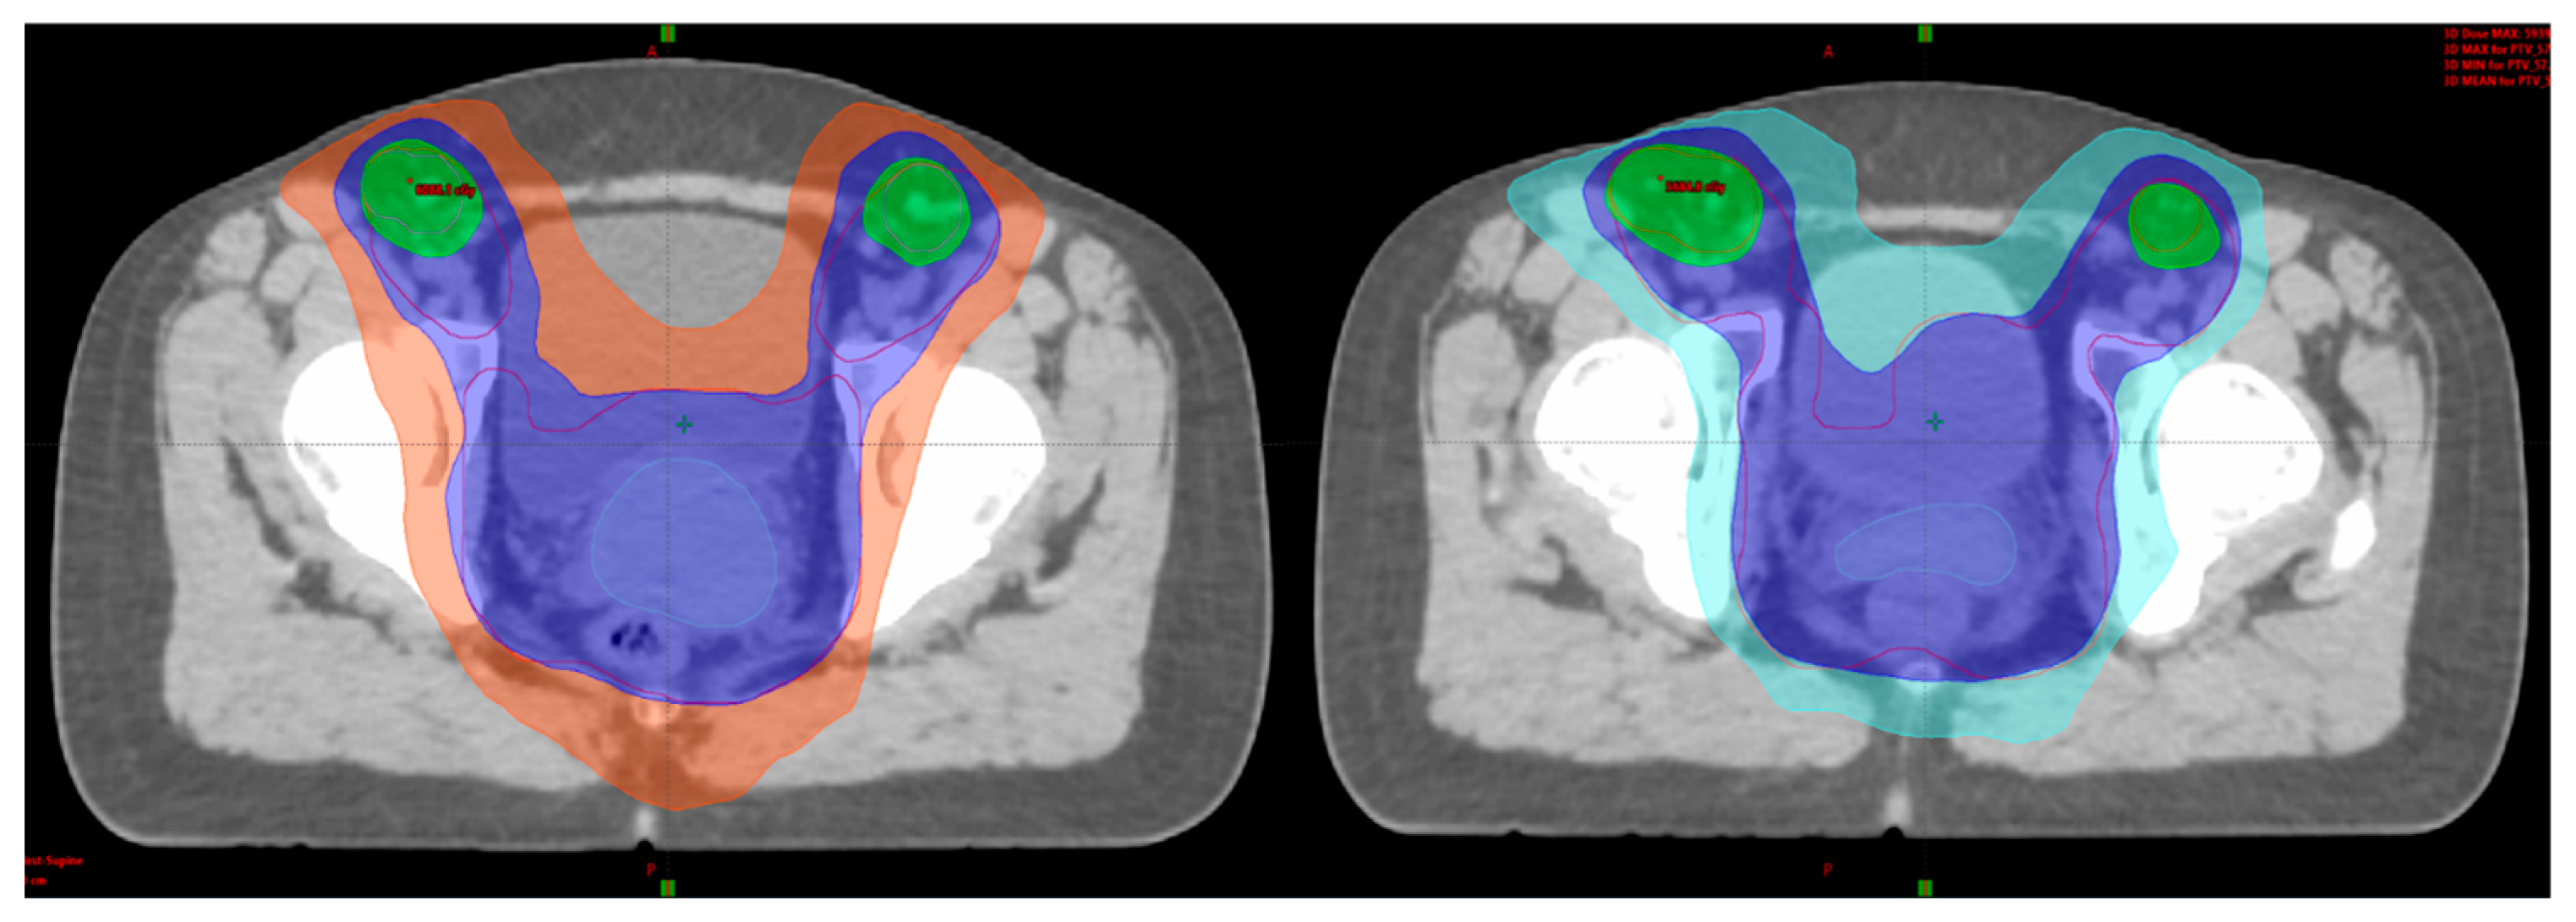

3.2. Intensity-Modulated Radiotherapy (IMRT) Volumetric Intensity-Modulated Arcs (VMAT)

3.3. Adaptive External Beam Radiotherapy

2. Imaging Modalities in Radiotherapy Planning